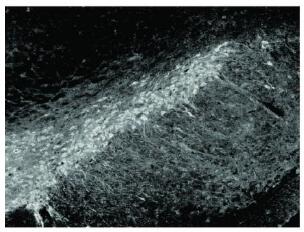

2.2 中脑黑质TH变化(图 1-4)![]() | 图 1 对照组可见大量TH+神经(10×) |

![]() | 图 2 LPS组可见TH + 神经元明显减少(10×) |

![]() | 图 3 LPS+ 30%鱼油组(10×) |

![]() | 图 4 LPS+ 60%鱼油组(10×) |

LPS组TH阳性细胞数为(71.66±7.08)个,与对照组(174.33±16.95)比较明显减少,仅为对照组的41%;而30%,60%鱼油组TH阳性细胞数是对照组的89%和90%,分别为(156.5±7.86)和(157±17.81)个。